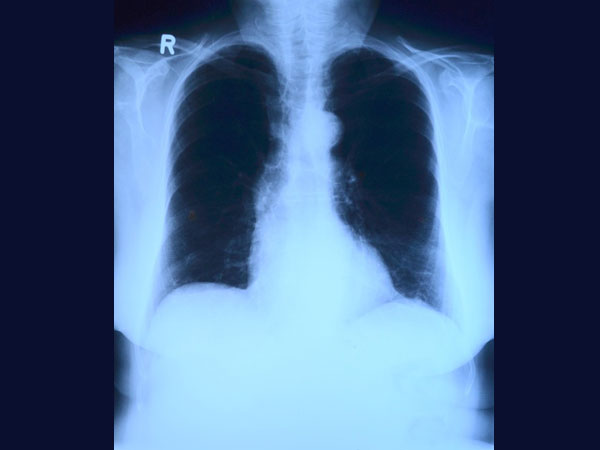

నవంబర్ 18న ఆయనకు తీవ్రమైన కడుపునొప్పి రావడంతో ఆసుపత్రి సిబ్బందికి అనుమానమొచ్చి ఎక్స్ రే తీశారు. అది చూసిన డాక్టర్లు నివ్వెరపోయారు. కడుపులో లోహపు నాణేలతో పాటు ఇతర వస్తువులు ఉన్నాయి. ఇదే కడుపునొప్పికి కారణంగా తేల్చారు.

మహమూద్ కడుపులోంచి వస్తువులను తీసేందుకు 6 నిష్ణాతులైన వైద్యులు శ్రమపడ్డారు. దాదాపు 5కేజీల వస్తువులు వారు తీశారు. 4 పెద్ద సూదులు, ఒక చెయిన్, 263 నాణేలు, 10 నుంచి 12 షేవింగ్ బ్లేడ్లు, కొన్ని గాజు ముక్కలను వారు కడుపులోంచి తీశారు. ఇలాంటి కేసును చూడటం తమ కెరీర్లోనే తొలిసారని డాక్టర్లు అన్నారు. ఆపరేషన్ను సరైన సమయంలో చేశామని ఒక డాక్టర్ అన్నాడు. అప్పటికే కొన్ని మేకులు లోపలి భాగాన్ని కుచ్చుకొని రక్తం స్రవించిందని చెప్పాడు.